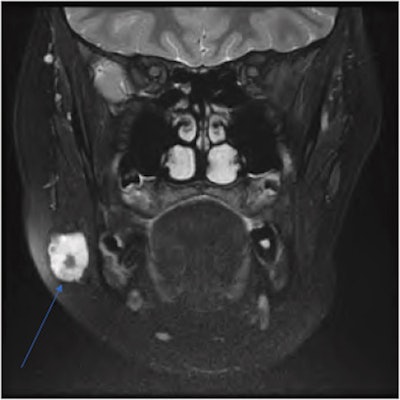

Attempts to conduct an ultrasound-guided biopsy failed because the needle wouldn't penetrate the lesion. Therefore, the patient underwent computed tomography (CT) and magnetic resonance imaging (MRI) of her neck, which showed an unusual lesion with calcification that appeared toothlike near the border of the girl's parotid gland and masseter muscle, the authors wrote.

Due to the lesion's unknown origin and concerns that it may be a possible neoplasm, a multidisciplinary team recommended an excision biopsy. The girl underwent a superficial parotidectomy to include the mass, which had multiple phleboliths clumped inside.